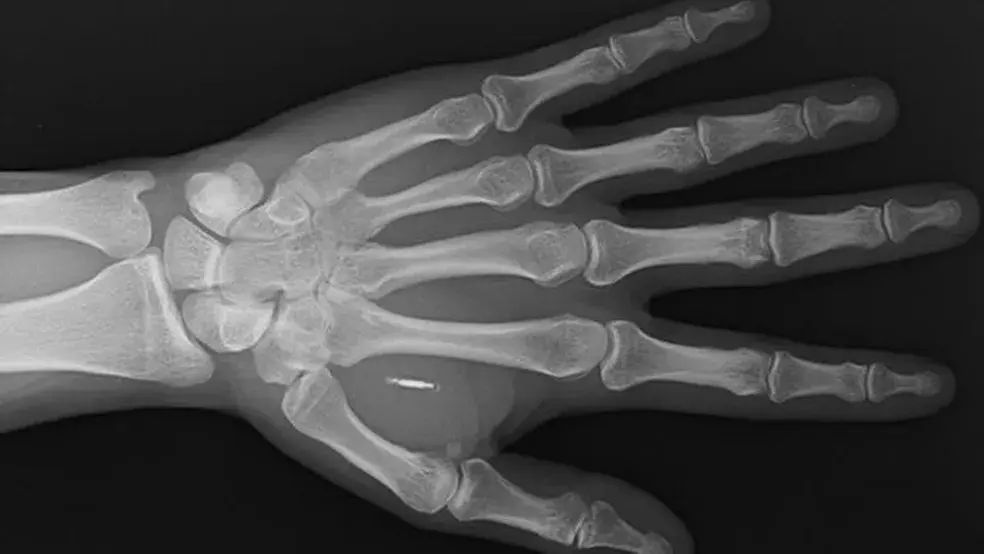

Um raio x mostrando um chip implantado na mão — Foto: WALLETMOR

Mas, em muitos casos, o conceito envolve implantes de microchips no corpo. Esses dispositivos têm circuitos eletrônicos e uma peça para se comunicar com outros aparelhos por ondas de rádio.

A Walletmor, empresa holandesa que trabalha com a tecnologia, diz que o chip é totalmente seguro, tem aprovação regulatória no país e funciona imediatamente após ser implantado. Também não requer bateria ou outra fonte.

O microchip é um conjunto de circuitos eletrônicos com módulos. Esses dispositivos costumam ser capazes de armazenar e transmitir informações.

Eles podem funcionar através de ondas de rádio, sensores integrados ou sinais elétricos. O chip pode ser implantado no corpo em poucos minutos e o processo geralmente acontece em estúdios de aplicação de piercing.

O microchip possui uma espécie de vidro que é biocompatível, ou seja, não cria reação alérgica ou outra reação imunológica, disse ao g1 Fernanda Matias, professora de biotecnologia na Universidade de São Paulo (USP). No Brasil, não há leis que regulamentam os implantes.